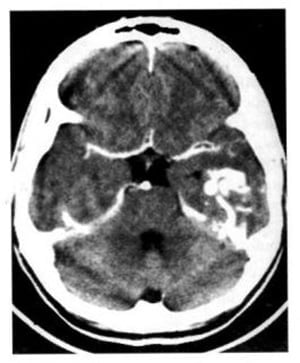

Hình 1.40. Nhồi máu não. Dưới 24 giờ, ảnh hưởng toàn bộ vùng chi phối của động mạch cảnh trong bên trái. Tổn thương mật độ thấp, giới hạn không rõ đẩy lệch não thất bên.